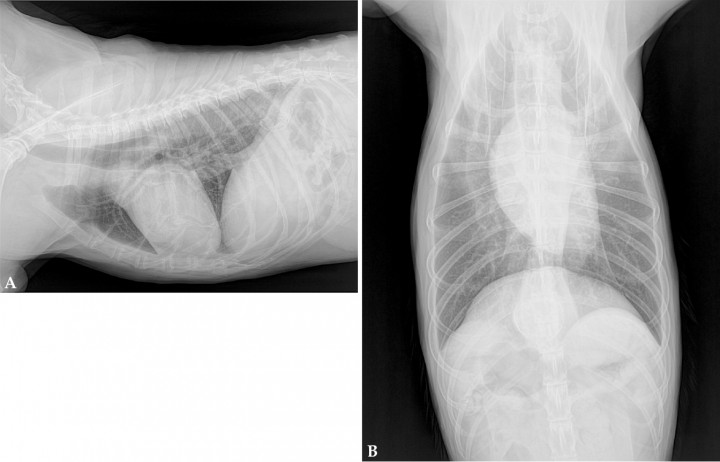

Se refiere al hospital una perra mestiza hembra esterilizada, de 13 años, con historia de vómitos y regurgitaciones esporádicas, de un mes y medio de evolución. Tanto el examen físico como la analítica sanguínea fueron normales sin revelar ninguna alteración. Se realizó un estudio radiográfico torácico para la evaluación del esófago incluyendo dos proyecciones: lateral derecha y ventrodorsal (Fig. 1).

<p>Radiografías de tórax de un perro con vómitos y regurgitaciones esporádicas de un mes y medio de evolución. (<strong>A</strong>) Proyección lateral derecha. (<strong>B</strong>) Proyección ventrodorsal.</p>

Figura 1

Radiografías de tórax de un perro con vómitos y regurgitaciones esporádicas de un mes y medio de evolución. (A) Proyección lateral derecha. (B) Proyección ventrodorsal.